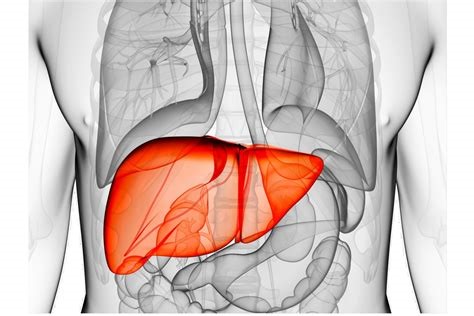

Cancer Cell | 首个肝细胞癌中TLS的全景发育图谱!Stereo-seq助力肝癌研究再获新突破